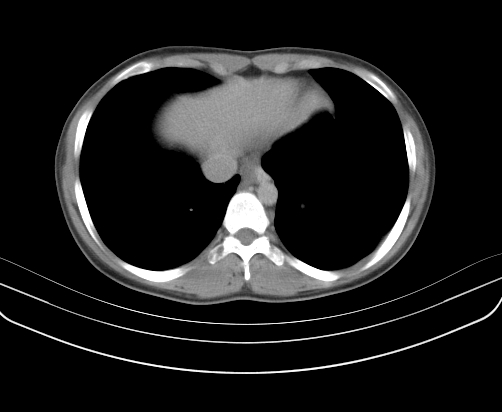

胸部